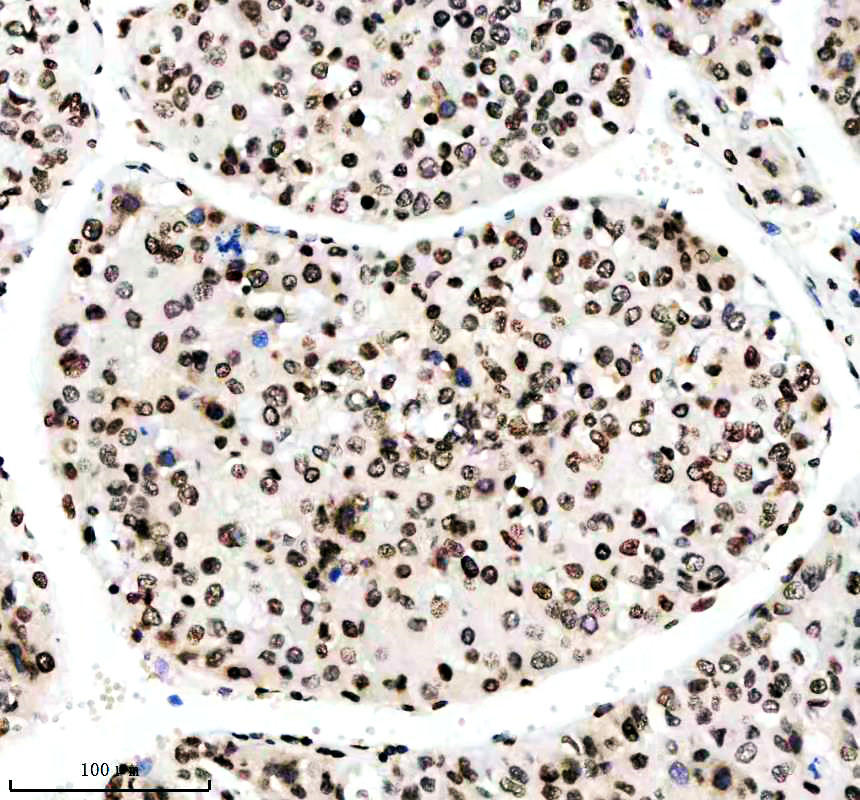

IHC analysis of Histone H3 (acetyl K14) using anti-Histone H3 (acetyl K14) antibody (BM4151) .

Histone H3 (acetyl K14) was detected in a paraffin-embedded section of human liver cancer tissue. The tissue section was incubated with rabbit anti-Histone H3 (acetyl K14) Antibody (BM4151) at a dilution of 1:200 and developed using HRP Conjugated Rabbit IgG Super Vision Assay Kit (Catalog # SV0002) with DAB (Catalog # AR1027) as the chromogen.